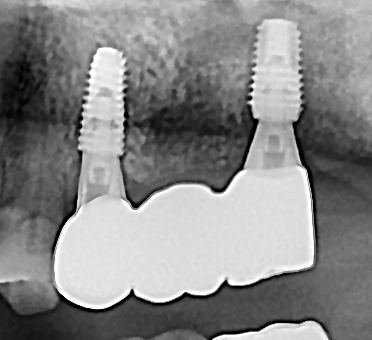

임플란트 뼈이식 + 임플란트